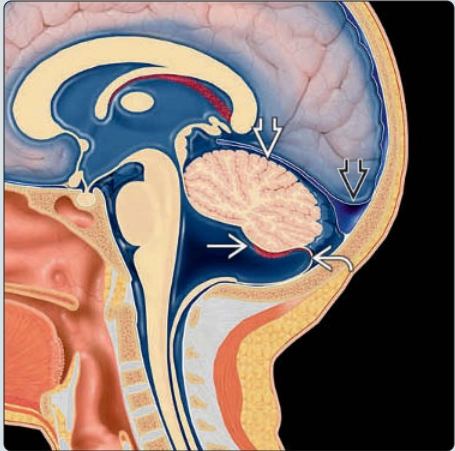

Dị dạng Chiari 2 thai nhi (Chiari 2 malformation)